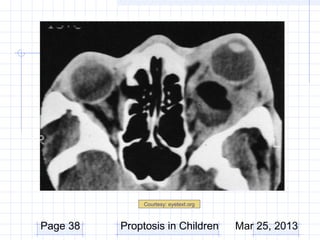

Work-up

CT/MRI

– Indicated if posterior extent not palpated

– Cystic appearance

– Well circumscribed lesion

Courtesy: eyetext.org

Page 38   Proptosis in Children        Mar 25, 2013